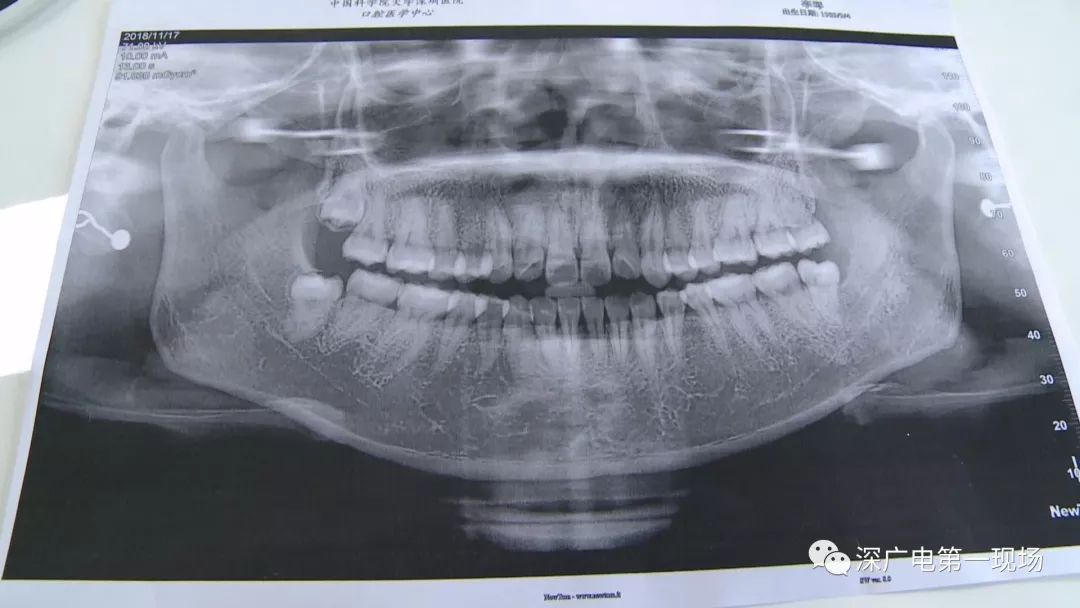

拔一顆智齒一千六?! 深圳這位女士默默的放下了賬單……

中國科學(xué)院大學(xué)深圳醫(yī)院口腔科主任賈岳介紹,對于不同患者的牙齒,它的治療方法都不一樣,所以不同牙齒,醫(yī)院收費的標準也各不相同。牙齒的治療方案,都是根據(jù)患者牙齒具體情況來制定,然后再去收費,同時也會參考病人實際情況來做不同的治療項目。